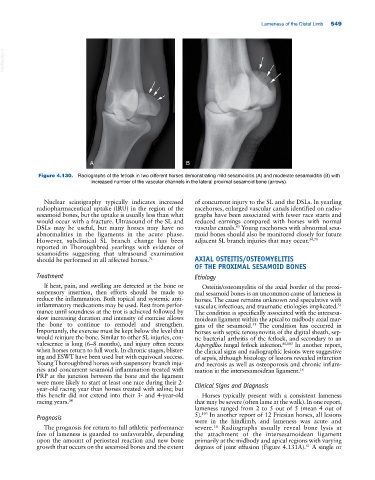

Figure 4.130. Radiographs of the fetlock in two different horses demonstrating mild sesamoiditis (A) and moderate sesamoiditis (B) with

increased number of the vascular channels in the lateral proximal sesamoid bone (arrows).